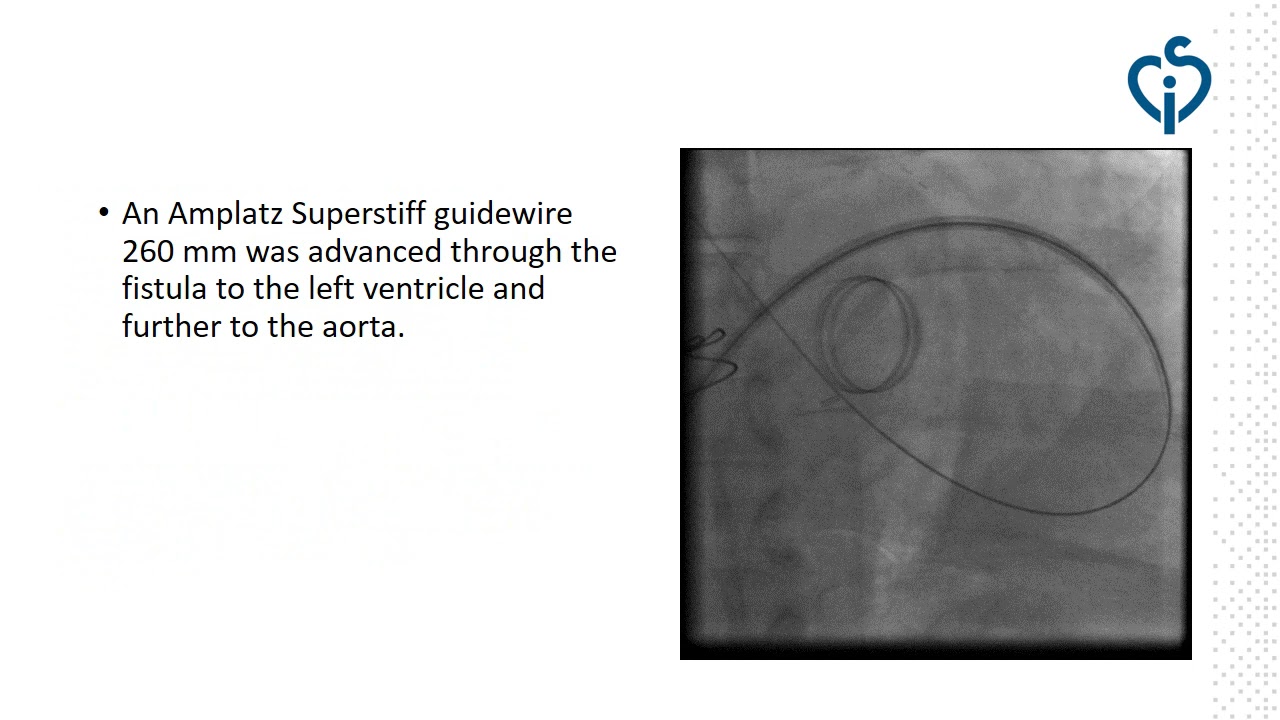

Transcatheter closure of recanalized large coronary-cameral fistula.

By: Lyubomir Dimitrov, National Heart Hospital, Sofia, Bulgaria